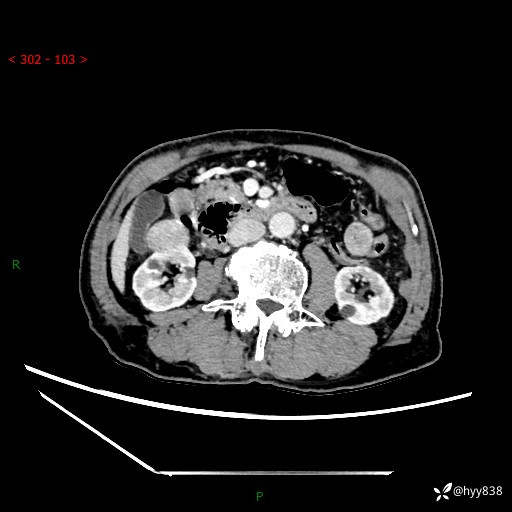

辅助检查:CT

肾脏CT平扫

增强(皮质期+髓质期+排泄期)

三期CT值:132hu 107hu 81hu